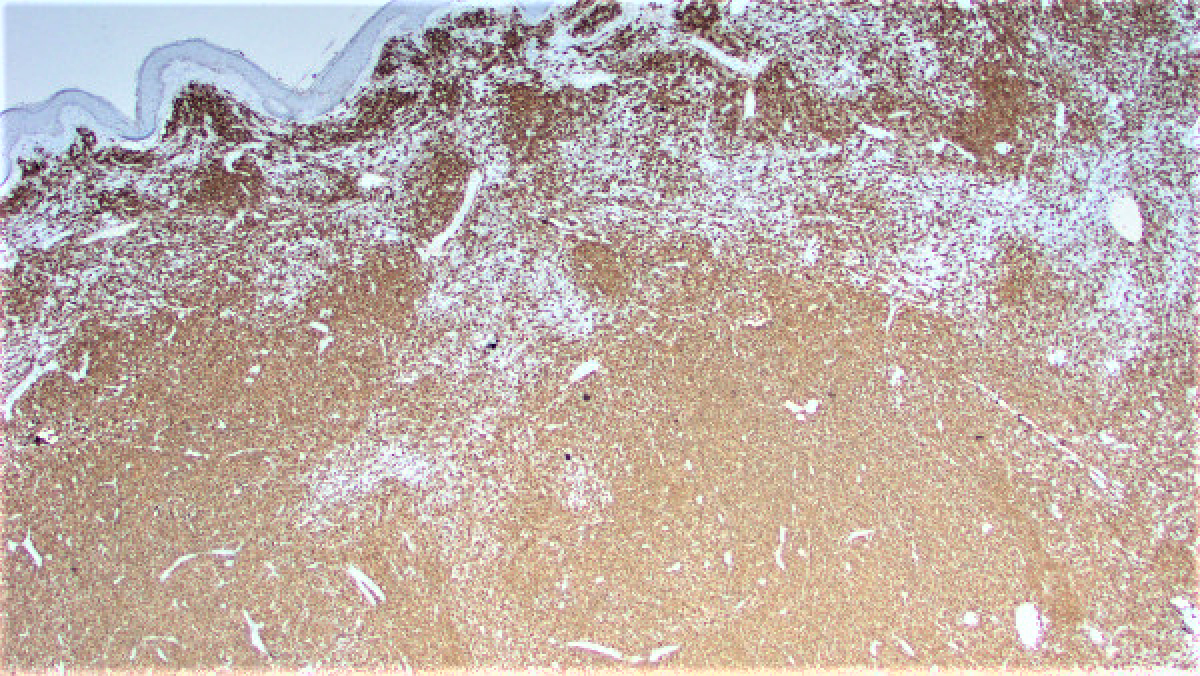

Three months ago the patient presented with a pink rash on the upper right arm. This was treated with topical steroids and the biopsy of that lesion revealed a reactive lymphoid proliferation. One month later the patient noticed a raised lesion on her upper right arm. An excisional biopsy of this lesion was performed. This biopsy revealed a vaguely nodular dermal infiltrate composed of a mixture of small cells with a high nuclear:cytoplasmic ratio and some larger cells with a plasmacytoid appearance (Figures 1 and 2). Immunohistochemical stains were performed and revealed both populations of cells to diffusely express CD20 (Figure 3) while negative for CD23 (Figure 4) and BCL-6 (Figure 5). There were scattered CD3 lymphocytes (Figure 6). Ki-67 was low (~20-30%), but elevated within residual germinal centers. Flow cytometry revealed lambda-restricted B cells, negative for CD5 and CD10.